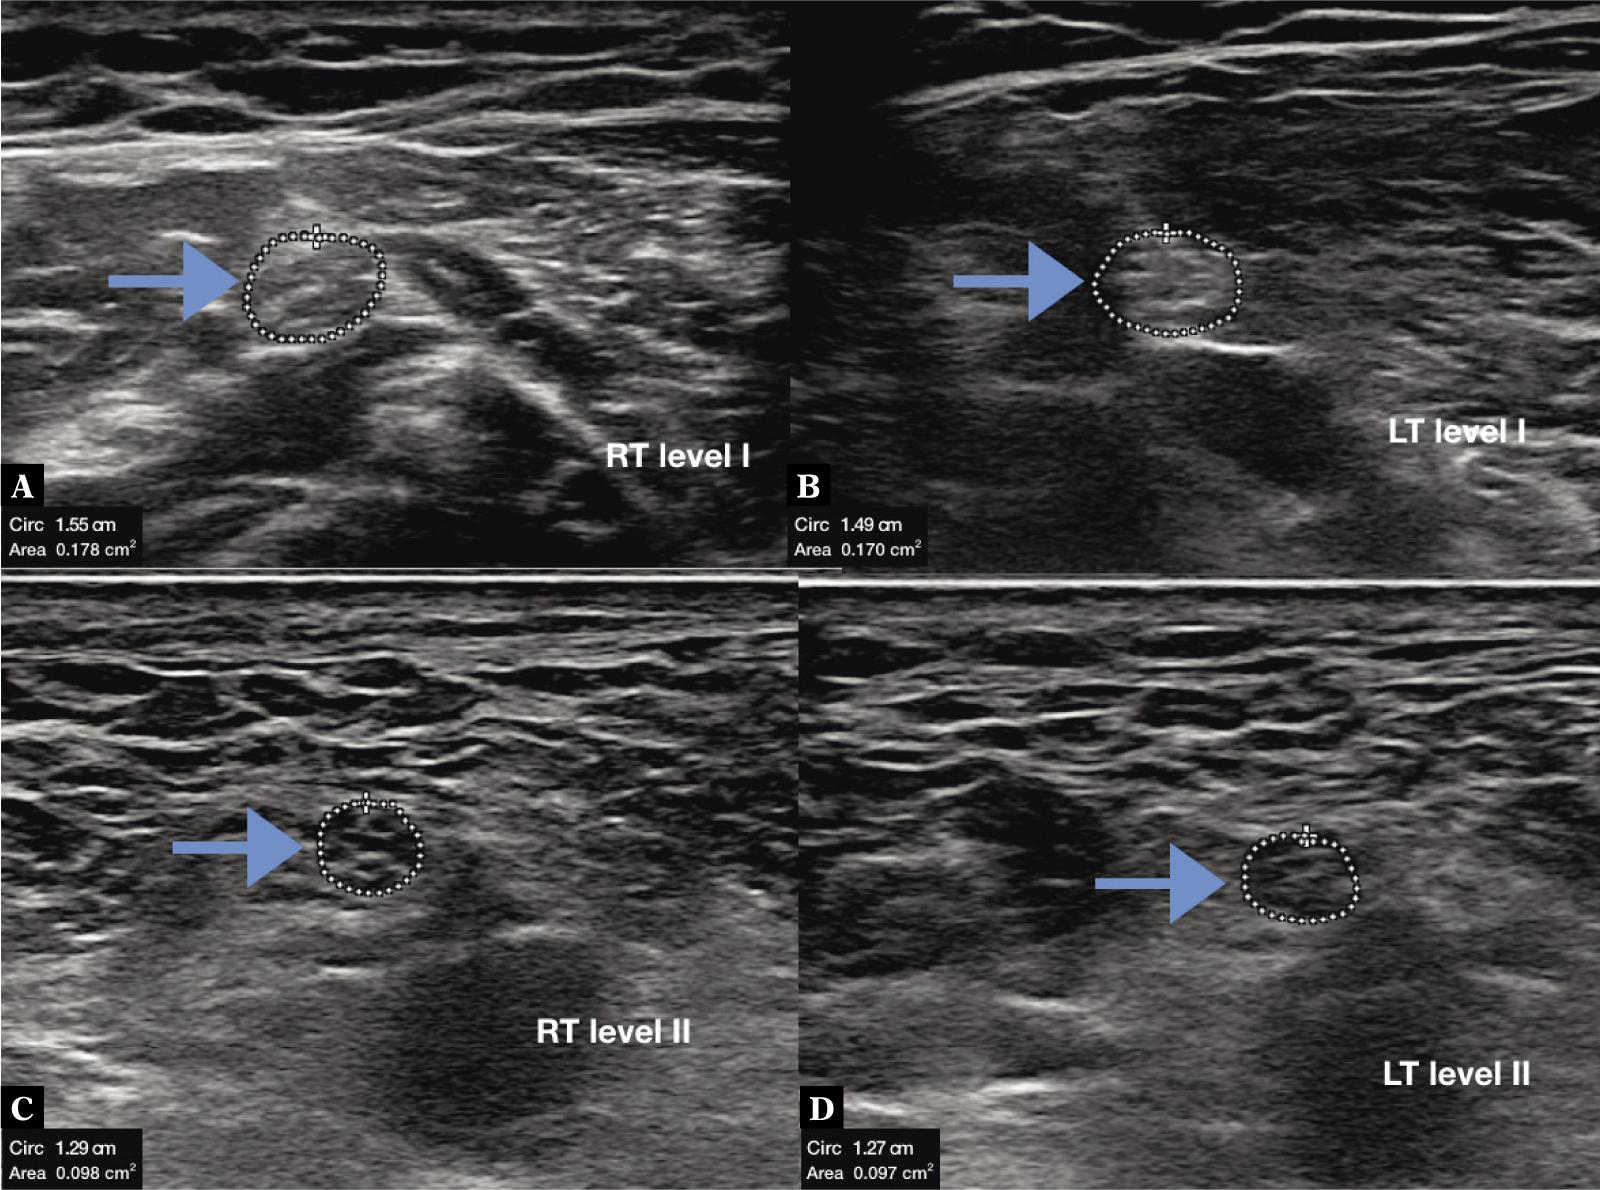

Fig. 2.

High-resolution ultrasonography of normal tibial nerve at level I (A, B) and II (C, D) in bilateral lower limb in 25 years old female weighing 46 kg, having height of 158 cm and body mass index of 19.1. Cross sectional area measured at level I was 0.178 cm2 and 0.170 cm2 and at level II was 0.098 cm2 and 0.097 cm2 in right and left lower limb, respectively (RT – right, LT – left, arrow – tibial nerve)